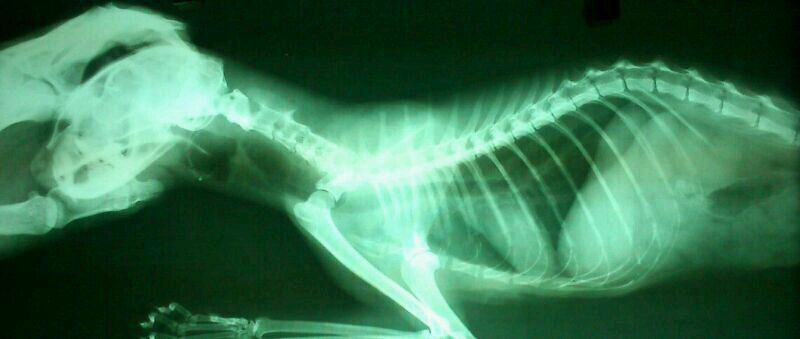

預計鼻胃管餵插管,插管後的x光檢查後發現鼻胃管無法進入食道

轉診其他醫院確診沾黏,建議安樂死

愛心媽媽不忍,自費帶至其他醫院預計進行食道切除重建手術